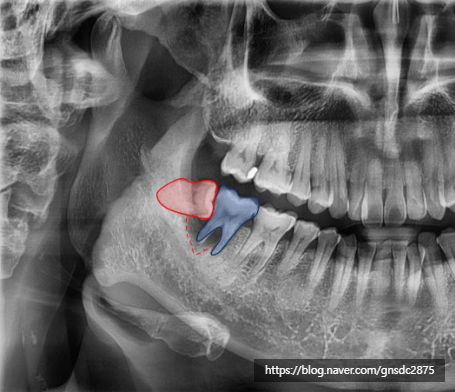

상태를 확인해보자

방치된 사랑니 주변 염증으로

옆 어금니의 잇몸뼈가 소실되어

뿌리가 지탱하지 못해 흔들리는 상태였습니다.

빨간색:사랑니 / 파란색:어금니 / 빨간선:소실된 잇몸

겉으로 보기엔 초기충치 정도만 진행되어

신경치료를 진행해 최대한 살리고 싶었지만

사랑니와 함께 옆어금니도 함께 발치하여

어금니는 뼈이식 후 임플란트를 하기로 결정했습니다.